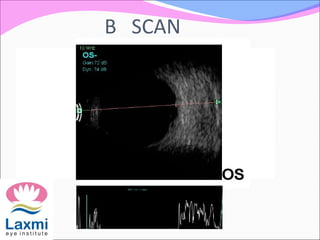

Features of B scan

Appears hyperechoic in contrast to clear vitreous

Sound attenuation is very strong . IOFB causes shadowing

of ocular and orbital structure behind it .

Associated ocular damage like vitreous haemorrhage,

retinal detachment can be assessed

USG localisation can tell position of even radiolucent

foreign body

B SCAN